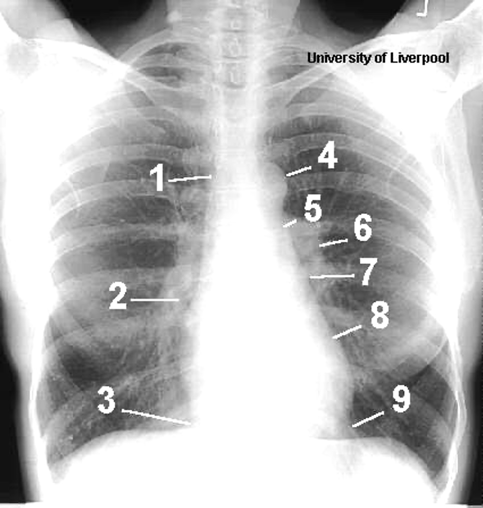

Name the mediastinal contours according to the numbers

1- superior vena cava

2- right atrium

3- inferior vena cava

4- aortic arch or knob

5- left pulmonary trunk

6- left pulmonary artery

7- left atrium

8- left ventricle

9- left cardiophrenic angle

Name the structures according to number